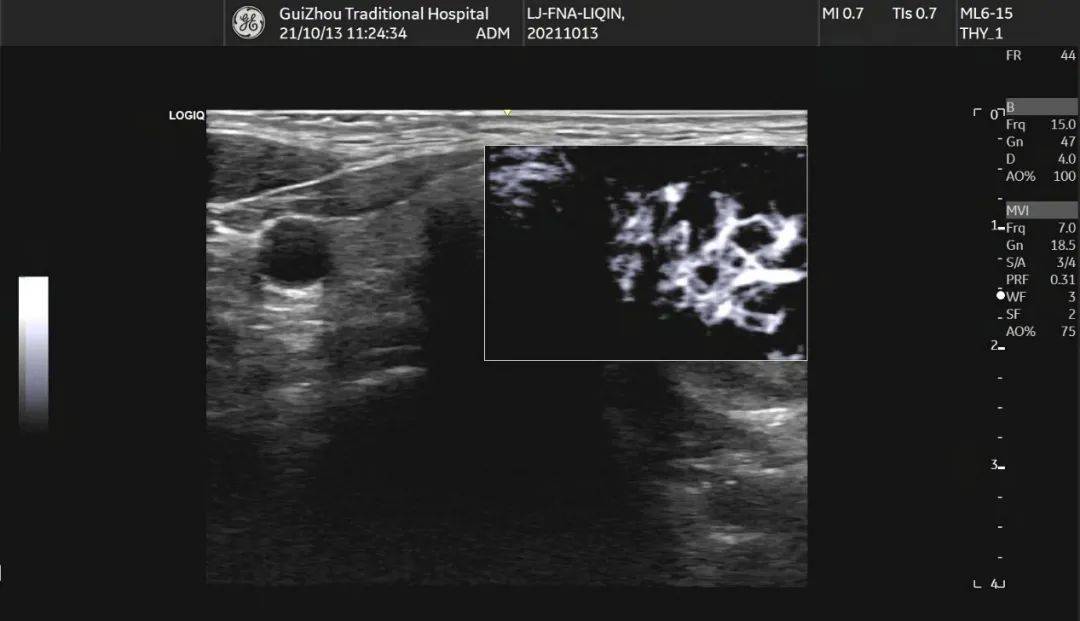

甲状腺形态失常,左侧叶增大,内部回声不均匀,见囊实混合性结节,大小约 33mm×19mm×28mm ,形态规则,边界清,纵横比 <1 ,内部以实性为主,实性部分见少许散在点状强回声(图 1 、图 2 ),结节周边伴低回声声晕,声晕厚度不均匀(图 3 ), CDFI:结节周边见环绕血流信号,内部见不规则分布的血流信号,局部较丰富(图 4 、图 5 )。SMI:结节局部微细血流信号丰富(图 6 )。

图 6 MVI 显示结节内部局部丰富血流